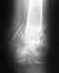

Доброго времени суток! Помогите разобраться в МРТ исследовании. Протокол исследования: В полости коленного сустава определяется умеренное количество избыточной жидкости, преимущественно в супрапателлярном завороте. Суставные поверхности деформированы мелкими единичными краевыми остефитами. Отмечается неравномерная зона остеосклероза субхондральных отделов медиальной поверхности надколенника. Гиалиновые хрящи равномерной толщины. Мениски уплощены. в структуре заднего рога внутреннего мениска выявляется малоинтенсивная, неполная косо-горизонтальная зона расслоения хряща. В медиальных отделах переднего рога внутреннего мениска обнаруживаются очаги хондромаляции. Явных признаков изменения структуры и разрыва наружного мениска не прослеживается. Передняя крестообразная связка с признаками внутриствольного повреждения в средних отделах, натянута, прослеживается на всем протяжении. Задняя крестообразная связка нормальнойтолщины. Боковые связки без очаговой патологии. Буду очень признателен адекватным комментариям. P.S.скажите на сколько все серьезно? Спасибо!